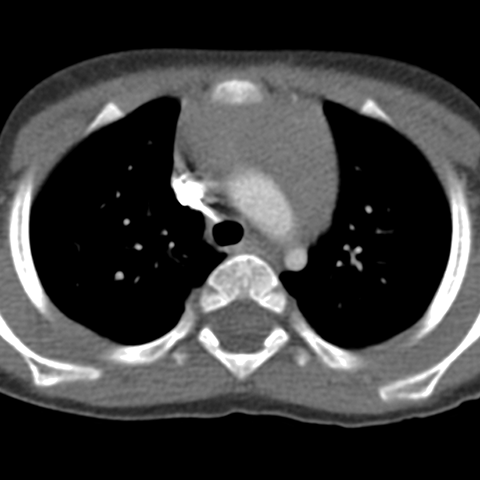

Thymus, 8 Months (Chest CT) [2 of 2]